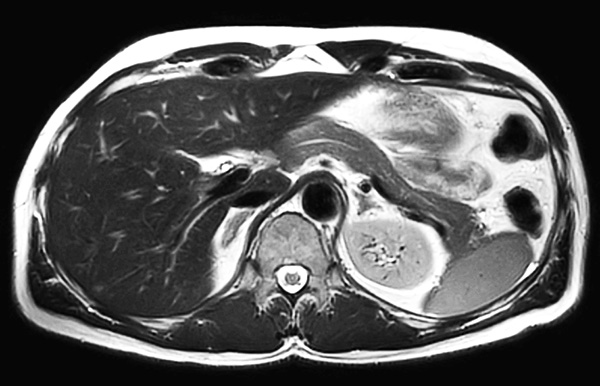

Axial T2w TSE